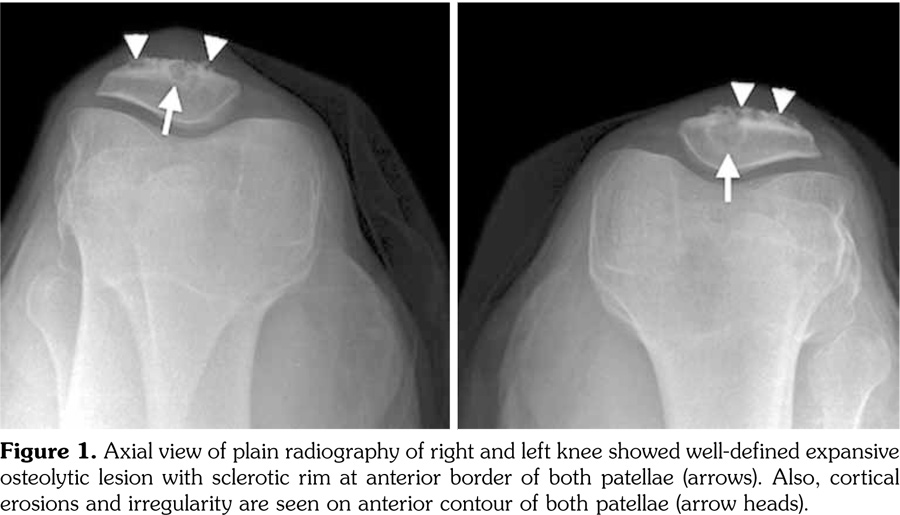

Laboratory tests including erythrocyte sedimentation rate, blood biochemistry, rheumatoid factor, anti-cyclic citrullinated peptide, liver function tests, and urinary analysis were normal except for uric acid value of 7.9 mg/dL (normal range 2.6-6.0 mg/dL) and C-reactive protein value of 2.1 mg/dL (normal range 0.01-0.82 mg/dL). Roentgenogram revealed lobulated, well-defined expansive osteolytic lesion with sclerotic rim at the anterior border of both patellae. The lesion in the right patella was 2x2.5 cm and the lesion in the left patella was 3x3 cm in diameter (Figure 1). Subsequent knee magnetic resonance imaging (MRI) showed bone marrow edema and well-defined expansive soft tissue lesions with low signal intensity on T1-weighted and high signal intensity on T2-weighted images (Figure 2a) in the anterior segments of the both patellae. Sagittal sequences demonstrated thickening and heterogeneous signal intensity in both patellar tendons (Figure 2b). The diagnosis of gouty involvement of the patella and patellar tendon was established according to the clinical, laboratory, and radiological findings. The patient was treated with colchicine 1 mg/day, and methylprednisolone 8 mg/day. Pain decreased in two weeks and he was able to resume his daily living activities more easily. Allopurinol 300 mg/day was started as urate-lowering therapy. Patient is under follow-up for five months and his serum uric acid level is 5.9 mg/dL.